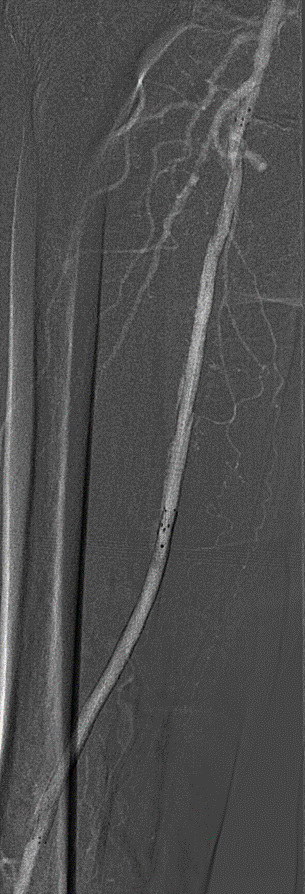

支架植入:遵循“由远及近”原则,先放置远端 DES,再覆盖中段 VB,最后处理近端。利用 Eluvia 的可调节性优化重叠。

DEC 策略为下肢动脉长段 CTO 病变提供了一种创新的腔内解决方案。初步15例经验表明:

其一年期通畅率值得肯定,部分病例甚至实现了两年以上的完美通畅;

能有效克服夹层、recoil 和内膜增生等核心难题;